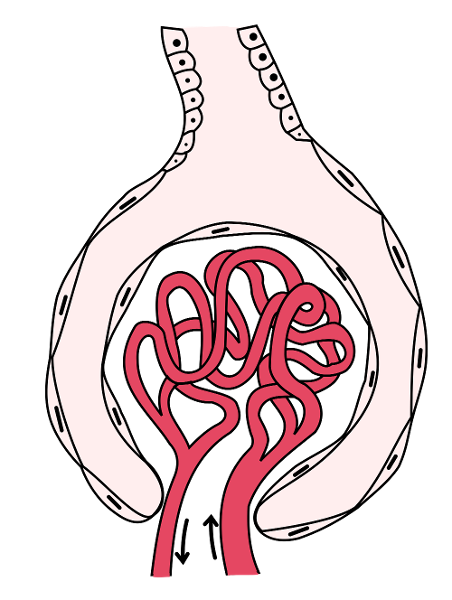

Afferent/efferent arteriole

Glomerular capsule (=Bowman's capsule)

Glomerulus (=glomerular capillaries)

Juxtaglomerular apparatus

Peritubular capillaries

Renal corpuscle